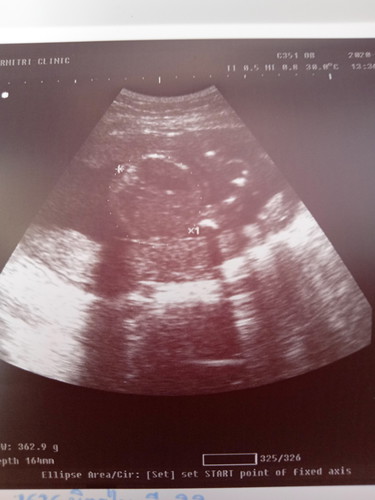

กลมๆ น่าจะหัว ส่วนยื่นๆ จากเลข 1 ไป น่าจะแขน

กลมๆคือรอบศรีษะน้องค่ะ

ภาพนี้เป็นหัวน้องคะ

เป็นภาพศรีษะลูกค่ะ